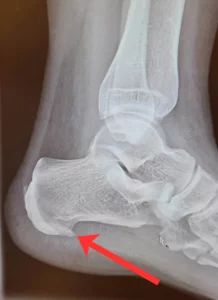

A saroksarkantyú (angolul heel spur) egy apró csontszerű kinövés a sarokcsont alsó részén, de megjelenhet ugyanez a probléma a talpi részen is. Ezen “meszes lerakódások” vagy “csontkinövések” és a kialakulási folyamat során, valamint a már kialakult kinövést jelző fájdalom gyakran a talpi fascia (vagy más néven talpi bőnye – egy vastag kötőszövetes szalag, amely a saroktól a lábujjakig fut a talp alsó részén) krónikus gyulladása miatt alakul ki. A fájdalom leginkább reggel, az első lépéseknél jelentkezik, majd napközben enyhülhet, de hosszabb távon akár állandó sarokfájdalomhoz is vezethet.